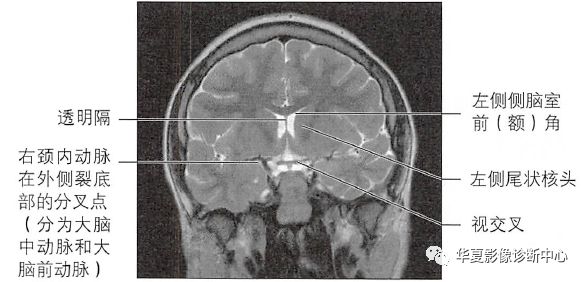

透明隔是含有神经纤维和灰质细胞的薄膜,位于两侧脑室之间并构成侧脑室的内壁,从侧面看,透明隔呈三角形,底在前方,尖端向后,其上方与胼胝体体部的下表面相贴,后部为穹隆与胼胝体的汇合点,后下方为前部穹隆,前下方为胼胝体嘴的上表面,正前方为胼胝体膝部。

Vergae腔位于胼胝体和后穹隆之间,上部和后部是胼胝体的体部与压部,前方和侧方是穹隆柱和体部,下方是穹隆联合,向后下延伸终止于穹隆脚附近。一般认为Vergae腔多为透明隔间腔向后扩展形成,但偶尔也可单独存在,形成原因可能是海马联合闭合不全。临床上Vergae腔常与透明隔间腔同时存在,并且互通,故统称为第五、六脑室;Vergae腔与脑室系统一般不相通。